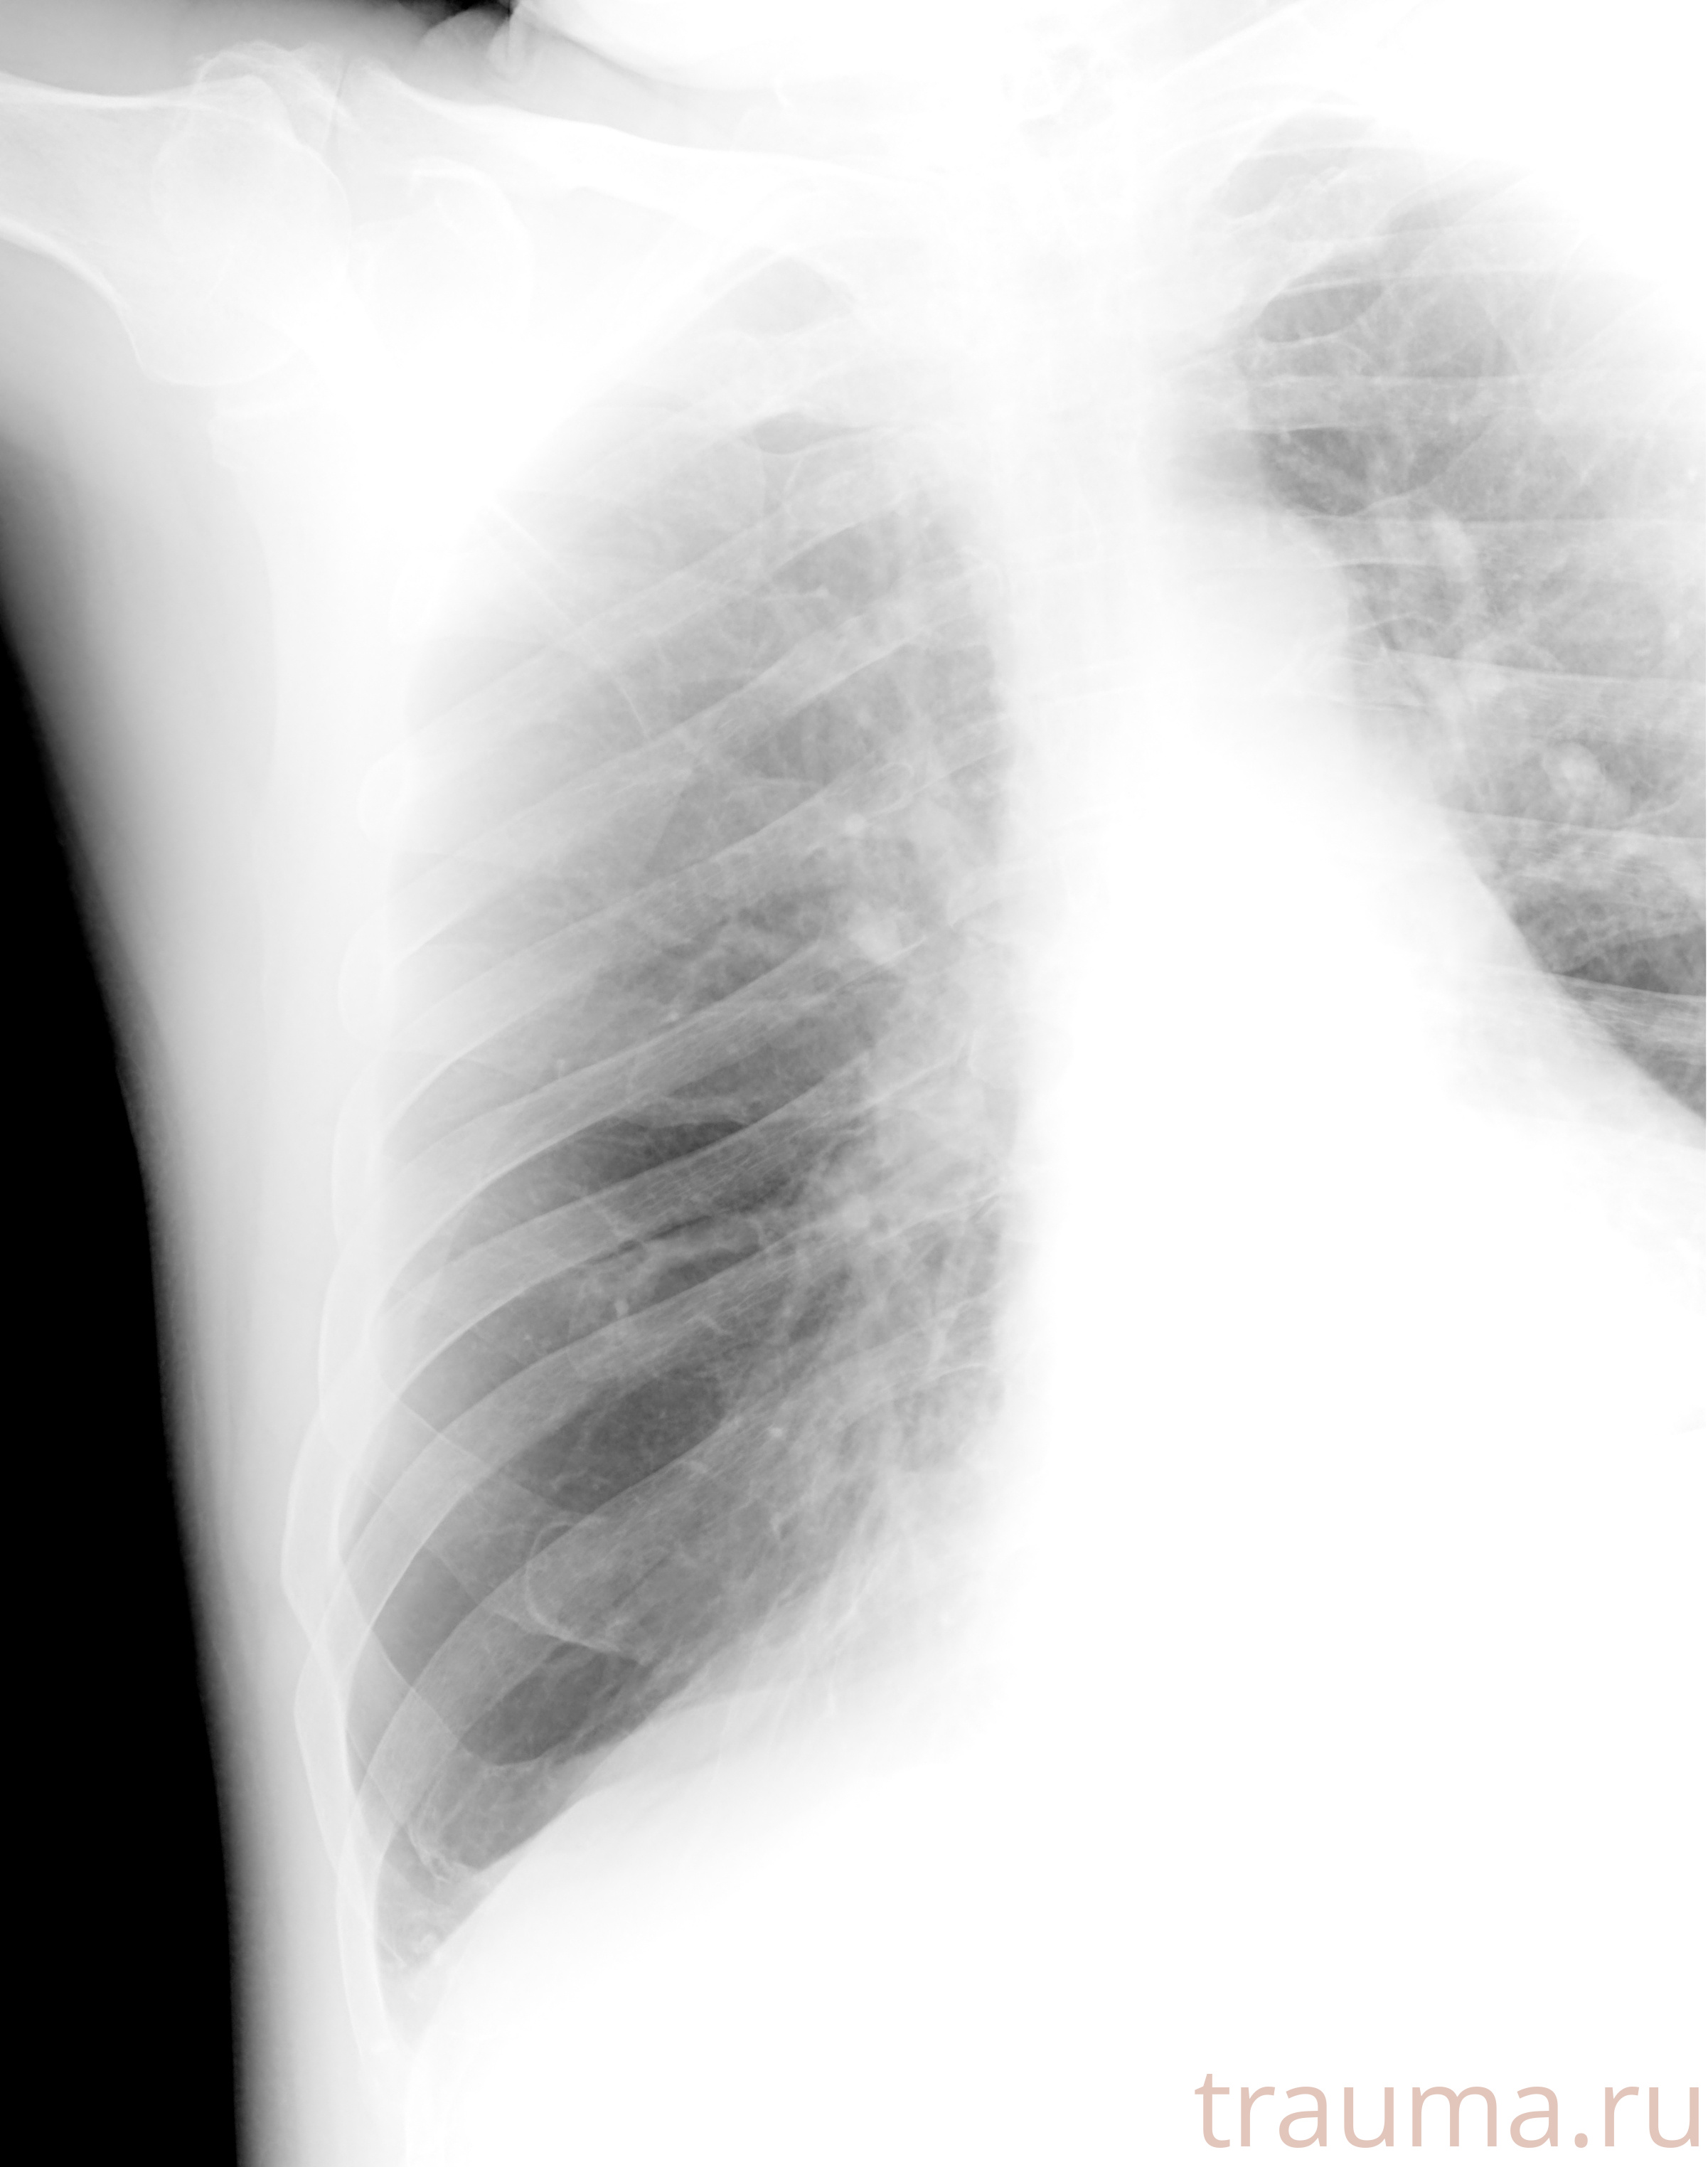

Рентгенограммы

Рентген на дому: по вашему адресу приезжает врач-рентгенолог, травматолог-ортопед с мобильным рентгеновским аппаратом, проводит диагностику травмы или заболевания, делает необходимые рентгенограммы, дает рекомендации по дальнейшему лечению. Получить качественные снимки в домашних условиях возможно благодаря уникальной методике, разработанной МосРентген Центром для института  Склифосовского

Яркость: 1   Контраст: 1   Инвертировать: 0 Увеличение: 1

Перетаскивайте мышь вверх/вниз для контраста, влево/право для яркости. Прокрутка колесом изменяет масштаб. Нажмите Сбросить для возврата к исходному изображению. При увеличении держите мышь в той области, которую хотите рассмотреть.